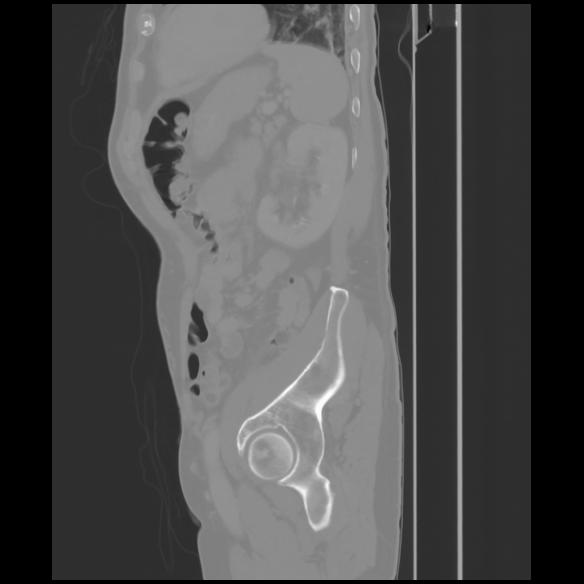

7 CUERPO,CE,Sagittal,3.000,CUERPO,Sagittal,